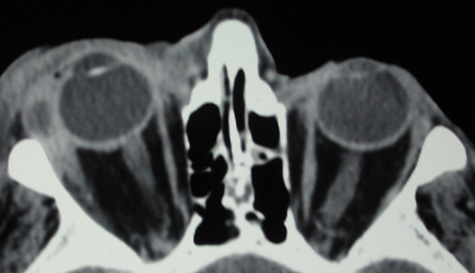

An extraconal or intraconal mass may be present in orbital cellulitis. Proptosis also may be visible. In particular, with intraconal involvement, proptosis is seen with obliteration of the normal soft tissue shadows. “Patchy enhancement” of the intraconal fat in orbital cellulitis has been described.59 The rectus muscles, particularly the medial rectus, and the optic nerve may be thickened.58

CT is particularly useful for imaging orbital and subperiosteal abscesses. Because the periorbit is not adherent to the orbital walls except at the suture lines, an abscess lifts the periorbit, creating a convexity in the orbital periosteum (Fig. 16). Usually subperiosteal abscess formation occurs adjacent to the involved sinus,25,64 but occasionally it occurs at a remote location such as the superolateral orbit.65 Gas may be found within a subperiosteal abscess or within the orbit, arising either from gas-forming bacilli or free communication with sinus air or from prior trauma (Fig. 17). 57,66 CT cannot accurately predict whether a subperiosteal mass represents exudate, inflammatory transudate, or hematoma.67,68

A subperiosteal abscess may rupture or invade the periorbit, resulting in an orbital abscess. This may or may not be contiguous with the subperiosteal collection on CT. There may be gas or air–fluid levels within the mass.51,56,58,59 An orbital abscess may present as an enhancing ringlike peripheral mass that can be either heterogeneous or homogeneous (Fig. 18).

Fig. 18. Orbital abscess. A. Computed tomography of an orbital abscess presenting as an enhancing intraconal mass on right side. B. T1-weighted image. C. T2-weighted image. Note area of high signal corresponding to abscess.